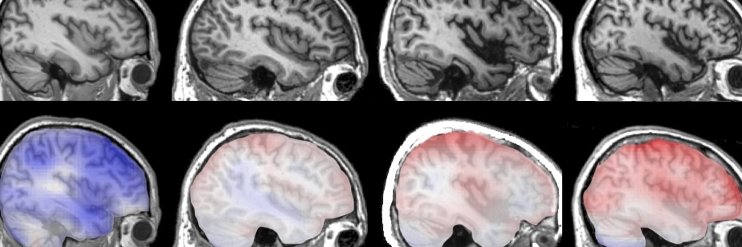

The ABATED study aims to validate novel AI technology for predicting dementia. Run by @charl_marshall @ainostics @preventiveneur1. Funded by @NIHRresearch.